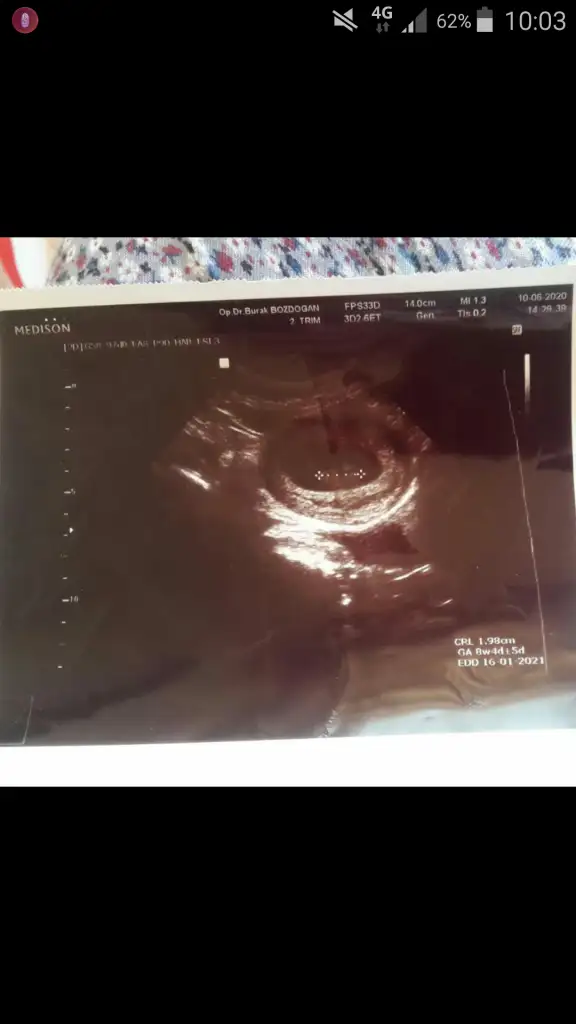

Canim bu var bideKız sanki başka USG varmı siyah beyaz USG teyit edeyim

Kız diyorlarda en iyi nub 11 12 13 hafta USG paylasin

15+ da nub olmaz boş görünüyor sanki kız gibi 11 12 13 haftalar olmalı nub icin

...Ikra meyra Merhabaa bana da tahmin yapabilir misiniz?

Kız gibi geldi banaIkra meyra Merhabaa bana da tahmin yapabilir misiniz?

Ikra kafayi yedim sanki isi gucu biraktim burda 8 9 haftalik usglere bakip kiyaslama yapiyom kiz ve erkek olanlari alip benimkiyle kiyasliyorum ama isin icinden cikamiyorum 8 haftalik hatta bugun 8+4 olduk ama persembe gunu dr 9+3 dedi yani bugun neredeyse 10 haftalik olcam ultrasona gore pandemi patladi burda korkumdan cikamiyorum disari meraktan siyirdim siyiricam :)Kız gibi geldi bana